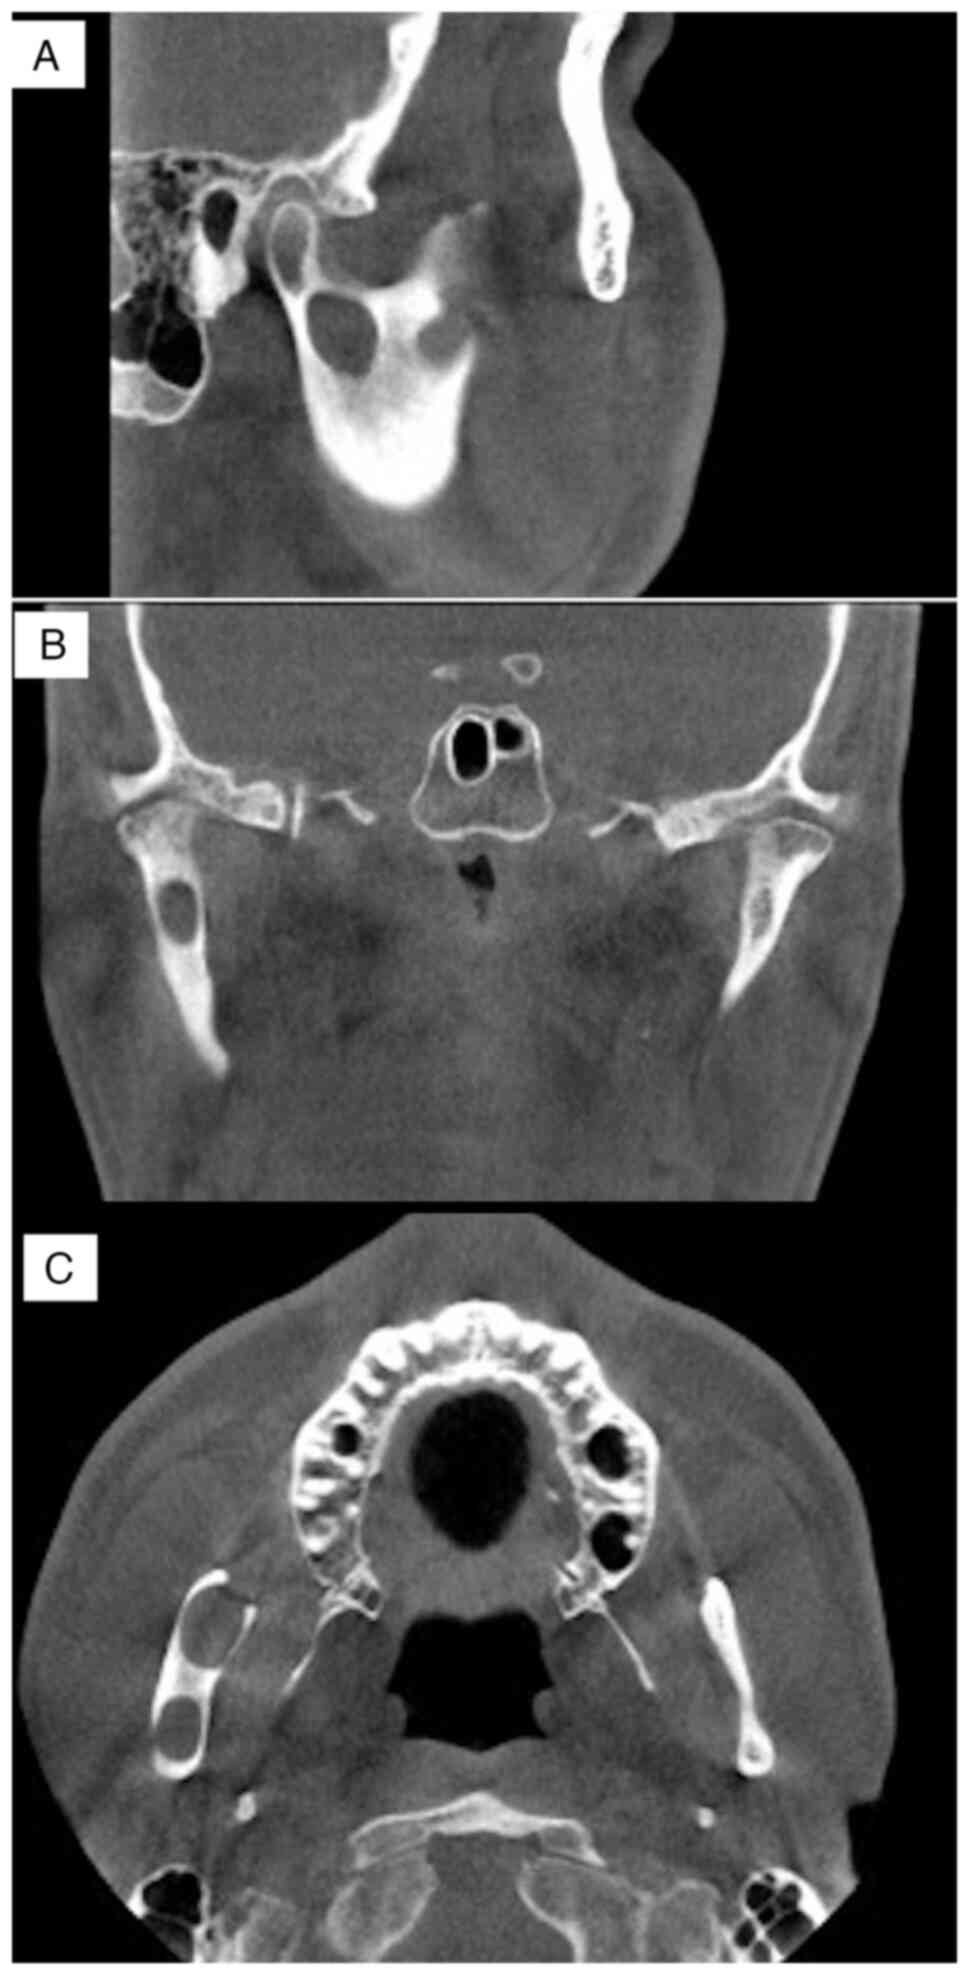

wisdom tooth was depressed owing to previous surgery (Fig. 2A and B). Panoramic radiographic examination

showed an isolated cyst-like transmission in the base of the

condyle and the anterior margin of the right mandibular ramus

(Fig. 3). Cone-beam computed

tomography examination disclosed a cyst-like transmission image

measuring 13x12x6 mm in the base of the condyle. A suspected

residual cyst was detected in the anterior margin of the right

mandibular ramus. The cysts were not connected and both were not in

contact with the inferior alveolar nerve (Fig. 4A-C). The long-term, continuous use